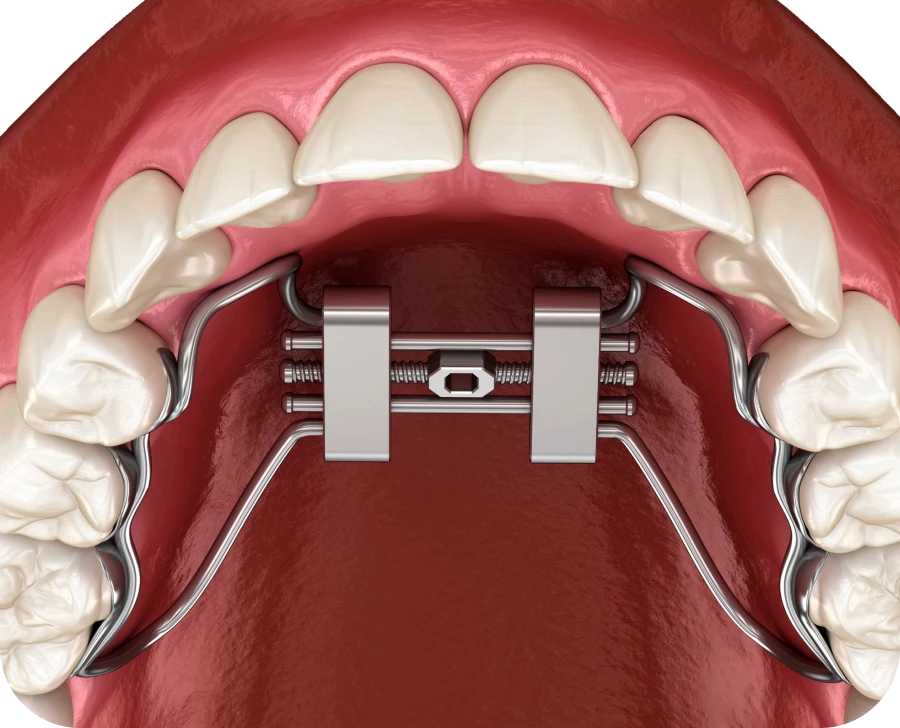

Comment fonctionne cet appareil orthodontique ?

L’orthodontiste fixe le disjoncteur sur les molaires supérieures. Un mécanisme central permet d’élargir progressivement le palais en tournant une vis de réglage. Cette activation est réalisée quotidiennement selon les instructions du praticien. Une activation progressive garantit un élargissement sans douleur excessive et respecte la croissance osseuse.

- Mode d’action du disjoncteur

Le disjoncteur applique une pression douce et constante sur les os du palais. Cette pression entraîne leur écartement progressif. Après quelques semaines, l’espace nécessaire pour les dents définitives est créé. Ce processus s’accompagne parfois de l’apparition d’un léger écart entre les incisives supérieures, un signe que le traitement fonctionne correctement.